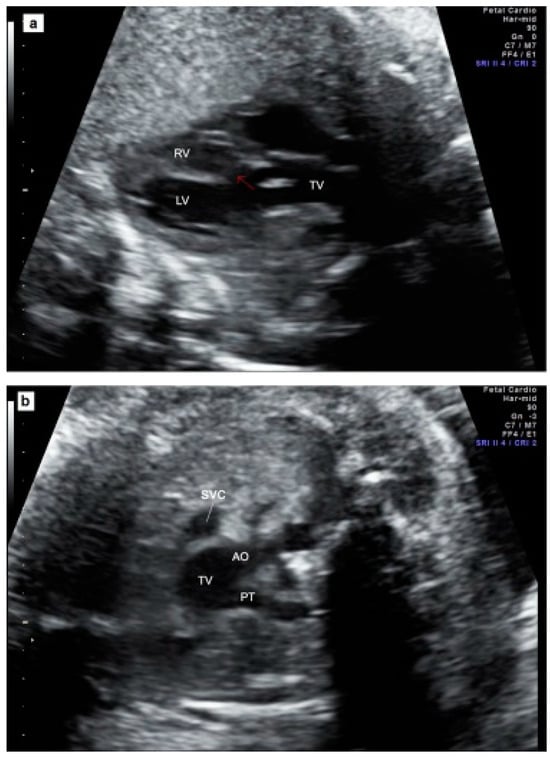

Figure 2 illustrates an example of a prenatal case with TAC. Parental counseling by pediatric cardiologists and geneticists was part of the prenatal work-up. Karyotyping including fluorescent in situ hybridization for 22q11.2 microdeletion was offered. The data were collected from medical files, as well as from stored ultrasound images and video loops, whenever they were available.

Figure 2.

Prenatal echocardiography of TAC. (a) The five-chamber view showing the presence of a thickened truncal valve that overrides a large VSD (arrow); (b) The three vessels view showing two vessels: superior vena cava and truncal vessel (subtype A1): pulmonary trunk arising from the truncal vessel); (c) example of subtype A4 in which aorta and MPA arise from the common arterial trunk and interrupted aorta divides into brachiocephalic and left common carotid arteries (IAA Type B). TV = truncal vessel; VSD = ventricular septal defect; LV = left ventricle; RV = right ventricle; PT = pulmonary artery trunk, Ao Asc = ascending aorta; Pulm Art = pulmonary artery; IAA = interrupted aortic arch.